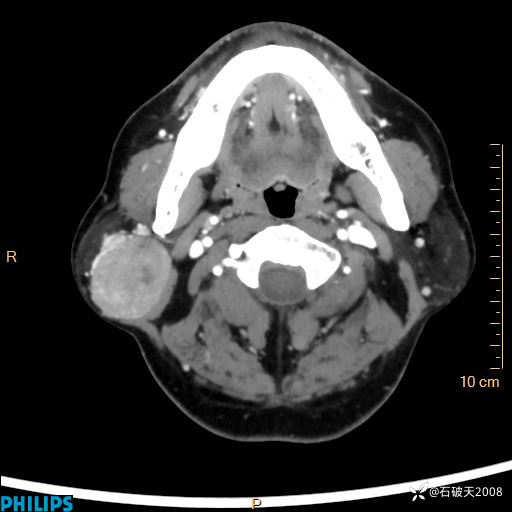

MIP